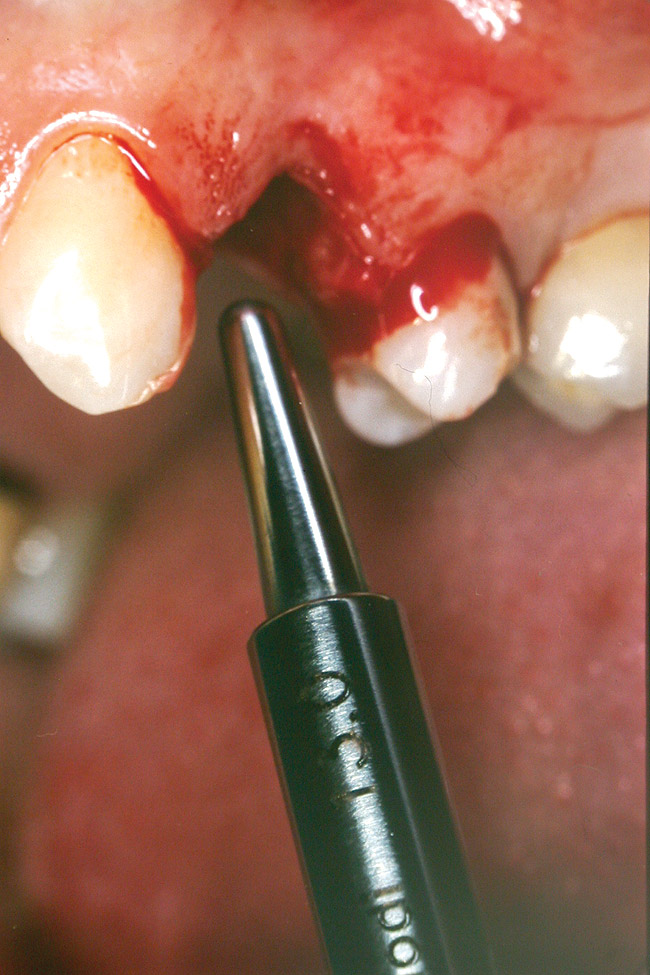

At the time of surgery, local infiltrative anesthesia was administered (lidocaine 2% with epinephrine, 1:100,000). A full-thickness mucoperiosteal flap was raised. The initial osteotomy was performed on midcrestal bone using a rose-headed bur. To prepare the osteotomy site for implant placement, sequential alternating osteotomes with variable conicity were used, drilling 2-mm shorter than the length of the implant to be placed (Figure 3A and Figure 3B). The implants presented initial primary stability (Figure 4), the cover screws were placed, and the implants were submerged for a healing period. The tissue was approximated, and the patient was instructed not to wear any denture or to place pressure on the healing site.

Figure 3a  Alternating osteotomes with variable conicity used to perform the alveolar remodeling in the area of tooth No. 24.

Figure 3a

Figure 3b  Alternating osteotomes with variable conicity used to perform the alveolar remodeling in the area of tooth No. 24.

Figure 3b